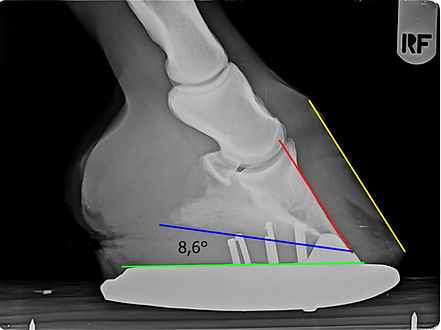

Obr. č. 9. a 10: RTG snímky před podkováním. Vyhodnocením snímků byl zjištěn na pravém kopytě (Obr. č. 9. vlevo) menší pokles kopytní kosti, větší rotace a o 3 mm silnější chodidlo než na levém kopytě (Obr. č. 10. vpravo). Proto bylo levé kopyto citlivější a bolestivější.

6. Dokumentace - RTG

RTG pravého předního kopyta před a po podkování

Obr. č. 32. a 33.:

RTG levého předního kopyta před a po podkování